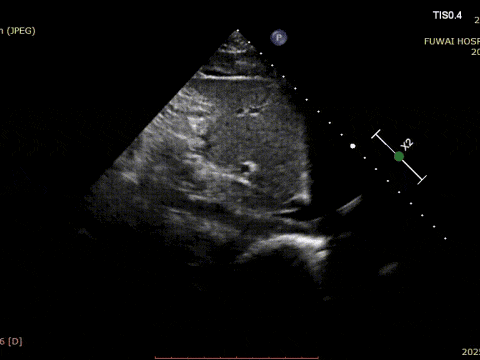

1. Die ASD war zentral in der Lage mit einem gemessenen Durchmesser von ungefähr 8,1mm (Bicaval-Ansicht) und 8,2mm (Aorten-Kurz achsen ansicht).

Das Verfahren wurde von TTE nach dem im Fuwai Hospital entwickelten PAN-Verfahren geleitet. Diese strahlungs freie Echtzeit-Bildgebung stech nik bietet eine hoch auflösende anatomische Visual isierung, die eine genaue Platzierung der Geräte gewähr leistet und Komplikationen minimiert-besonders wertvoll bei jungen Patienten im reproduktiven Alter.